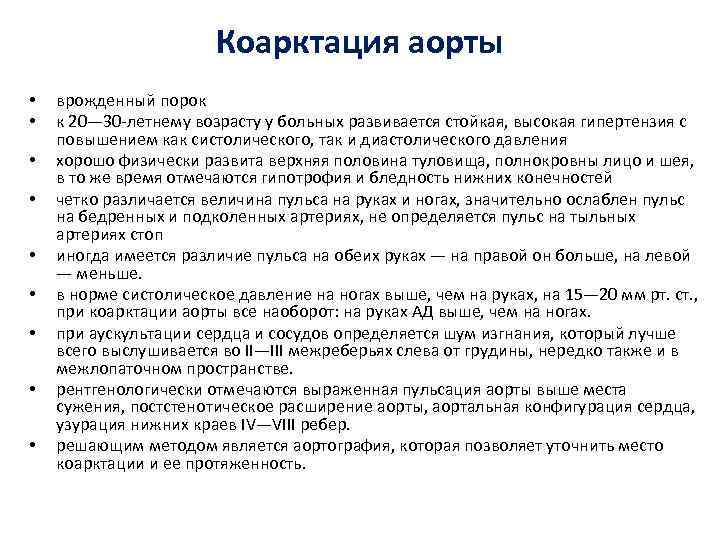

Коарктация аорты • • • врожденный порок к 20— 30 -летнему возрасту у больных развивается стойкая, высокая гипертензия с повышением как систолического, так и диастолического давления хорошо физически развита верхняя половина туловища, полнокровны лицо и шея, в то же время отмечаются гипотрофия и бледность нижних конечностей четко различается величина пульса на руках и ногах, значительно ослаблен пульс на бедренных и подколенных артериях, не определяется пульс на тыльных артериях стоп иногда имеется различие пульса на обеих руках — на правой он больше, на левой — меньше. в норме систолическое давление на ногах выше, чем на руках, на 15— 20 мм рт. ст. , при коарктации аорты все наоборот: на руках АД выше, чем на ногах. при аускультации сердца и сосудов определяется шум изгнания, который лучше всего выслушивается во II—III межреберьях слева от грудины, нередко также и в межлопаточном пространстве. рентгенологически отмечаются выраженная пульсация аорты выше места сужения, постстенотическое расширение аорты, аортальная конфигурация сердца, узурация нижних краев IV—VIII ребер. решающим методом является аортография, которая позволяет уточнить место коарктации и ее протяженность.

Коарктация аорты • • • врожденный порок к 20— 30 -летнему возрасту у больных развивается стойкая, высокая гипертензия с повышением как систолического, так и диастолического давления хорошо физически развита верхняя половина туловища, полнокровны лицо и шея, в то же время отмечаются гипотрофия и бледность нижних конечностей четко различается величина пульса на руках и ногах, значительно ослаблен пульс на бедренных и подколенных артериях, не определяется пульс на тыльных артериях стоп иногда имеется различие пульса на обеих руках — на правой он больше, на левой — меньше. в норме систолическое давление на ногах выше, чем на руках, на 15— 20 мм рт. ст. , при коарктации аорты все наоборот: на руках АД выше, чем на ногах. при аускультации сердца и сосудов определяется шум изгнания, который лучше всего выслушивается во II—III межреберьях слева от грудины, нередко также и в межлопаточном пространстве. рентгенологически отмечаются выраженная пульсация аорты выше места сужения, постстенотическое расширение аорты, аортальная конфигурация сердца, узурация нижних краев IV—VIII ребер. решающим методом является аортография, которая позволяет уточнить место коарктации и ее протяженность.